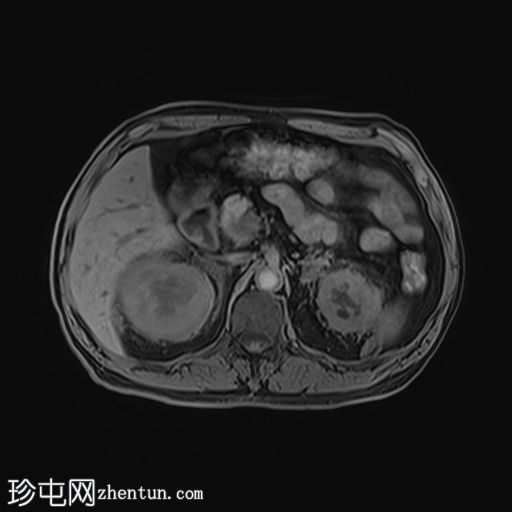

轴位

DWI

双肾包膜及肾周软组织增厚,呈光滑对称性,后侧及右侧更为明显。增厚延伸至肾门及近端输尿管周围,导致轻度双侧肾积水。左侧肾周可见局灶性纤维化带,可能为局灶性纤维化。整体影像学表现提示肾周纤维化或浸润性病变。

左肾相对较小,皮质轻度变薄,下极可见两个边界不清、T2信号低、无限制性病变。这些病变可能与纤维化灶或肿瘤(例如乳头状肾细胞癌和淋巴瘤)相符。右肾实质厚度正常,未见局灶性病变。

双侧肾上腺肿大,伴软组织增厚,但未见明显肿块。

Erdheim-Chester病(ECD)是一种罕见的非朗格汉斯细胞组织细胞增生症,其特征是多个器官出现黄色肉芽肿性浸润。典型的肾脏受累表现为双侧对称性肾周软组织增厚,常累及肾门和近端输尿管周围。肾上腺周围浸润也较为常见。

左肾的病变可能是与该病相关的纤维化肾实质内病变,也可能是肿瘤性病变,例如肾乳头状细胞癌或淋巴瘤。需要进一步评估。